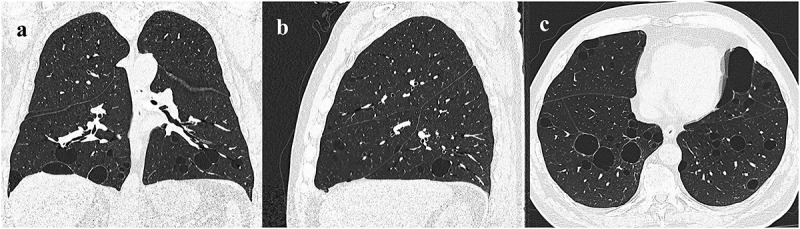

Results: A total of 101 patients (44 men (43.6%); mean age 48.4 years (SD ± 15.9 years)) with BHD were included. Chest HRCT scans revealed pulmonary cysts in 82.2% of whom 38.6% had experienced at least one pneumothorax (median 2; IQR1-4). Baseline PFT showed FEV1/FVC ratio and RV% within normal values of predicted. In 28.7% of the patients, a slight decrease in DLco below 80% of predicted was observed (mean 86.9% ± SD 15.8%). At two years follow-up, there were no significant declines in FEV1 and FVC, nor after accounting for age, gender, and smoking. At baseline cutaneous manifestations were found in 58.4% of the patients, 47.5% had benign renal cysts, and 11.9% had renal tumours.

Conclusion: More than 80% of patients with BHD presented with pulmonary cysts, but consistent with other studies all had normal PFTs at two years follow-up. We conclude that routine monitoring of pulmonary function and pulmonary follow-up may not be necessary in patients with BHD.